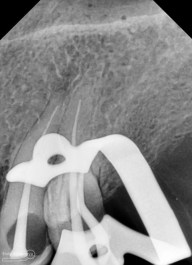

Setelah akses ke kamar pulpa didapat, lalur dirapihkan agar arah masuk file dapat lurus, maka selanjutnya adalah proses cleaning and shaping… Panjang kerja diukur menggunakan apex locator Root ZX mini (Morita) dan preparasi saluran akar menggunakan i3 Gold (Denjoy)… Irigasi memakai larutan NaOCl 5,25% dan diaktivasi menggunakan waterpik dan tip endoactivator…

Setelah proses cleaning and shaping dilakukan trial gutta percha untuk melihat apakah kon utama yang akan kita gunakan pas dengan saluran akarnya…

Setelah melihat hasil ronsen trial guttap maka pengisian siap dilakukan… Untuk pengisian saluran akar saya memakai tehnik warm vertival condensation memakai alat Element Obturation Unit (SybronEndo) dan siler AH plus (Dentsply)…